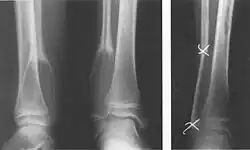

Aneurysmatische Knochenzyste, Kontinuitätsresektion (Fibula)

• Einfache (juvenile) Knochenzyste: Gutartige, primär einkammerige, flüssigkeitsgefüllte Höhle, meist im metaphysären Markraum. Wird meist erst durch Spontanfraktur auffällig. Klassisches Röntgenzeichen ist das Fallen-Fragment-Sign.

• Einfache (juvenile) Knochenzyste: Das heute etablierte Verfahren ist die intramedulläre Osteosynthese (Prevot-Nagelung) des Knochens. Hierbei wird eine in einigen Fällen entstandene Fraktur stabilisiert, die Knochenzyste erhält gleichzeitig einen Reiz auszuheilen. Einige Gruppen verwenden zur Ausheilung nicht frakturierter juveniler Zysten noch eine Injektion von Cortison-Lösungen oder eine Perforation mit Eröffnung der Zystenwand.